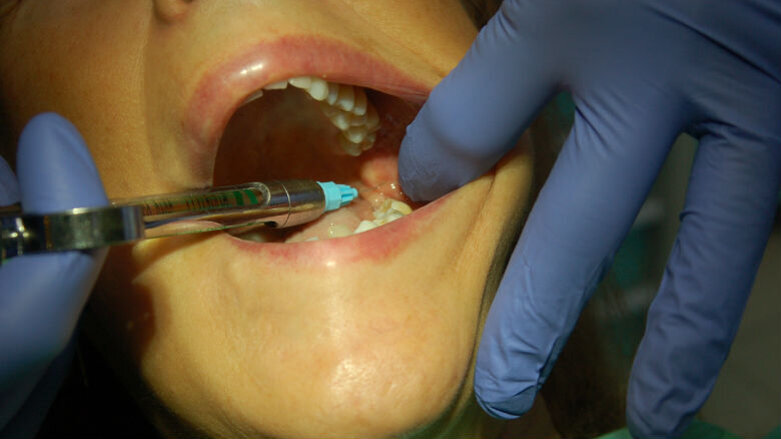

È quindi opportuno che un anestetico topico venga preliminarmente usato per rendere la fase di iniezione la meno sgradevole possibile, che l’iniezione venga eseguita applicando la giusta pressione, in modo da non sovradistendere i tessuti molli (una delle causa di dolore) e che sia fatta nel corretto sito anatomico (Figg. 1, 2). Il tempo di iniezione raccomandato è 1 ml/minuto. Tuttavia, l’84% dei dentisti inietta 1,8 ml in 20 secondi o meno. Inoltre la molecola opportuna per l’intervento programmato dovrà essere selezionata in base alla durata attesa della sua azione e, quindi, della sua efficacia, prestando attenzione anche alla quantità di vasocostrittore presente e alla condizione di salute generale del paziente.

Fig. 2 - Anestesia del nervo buccale.